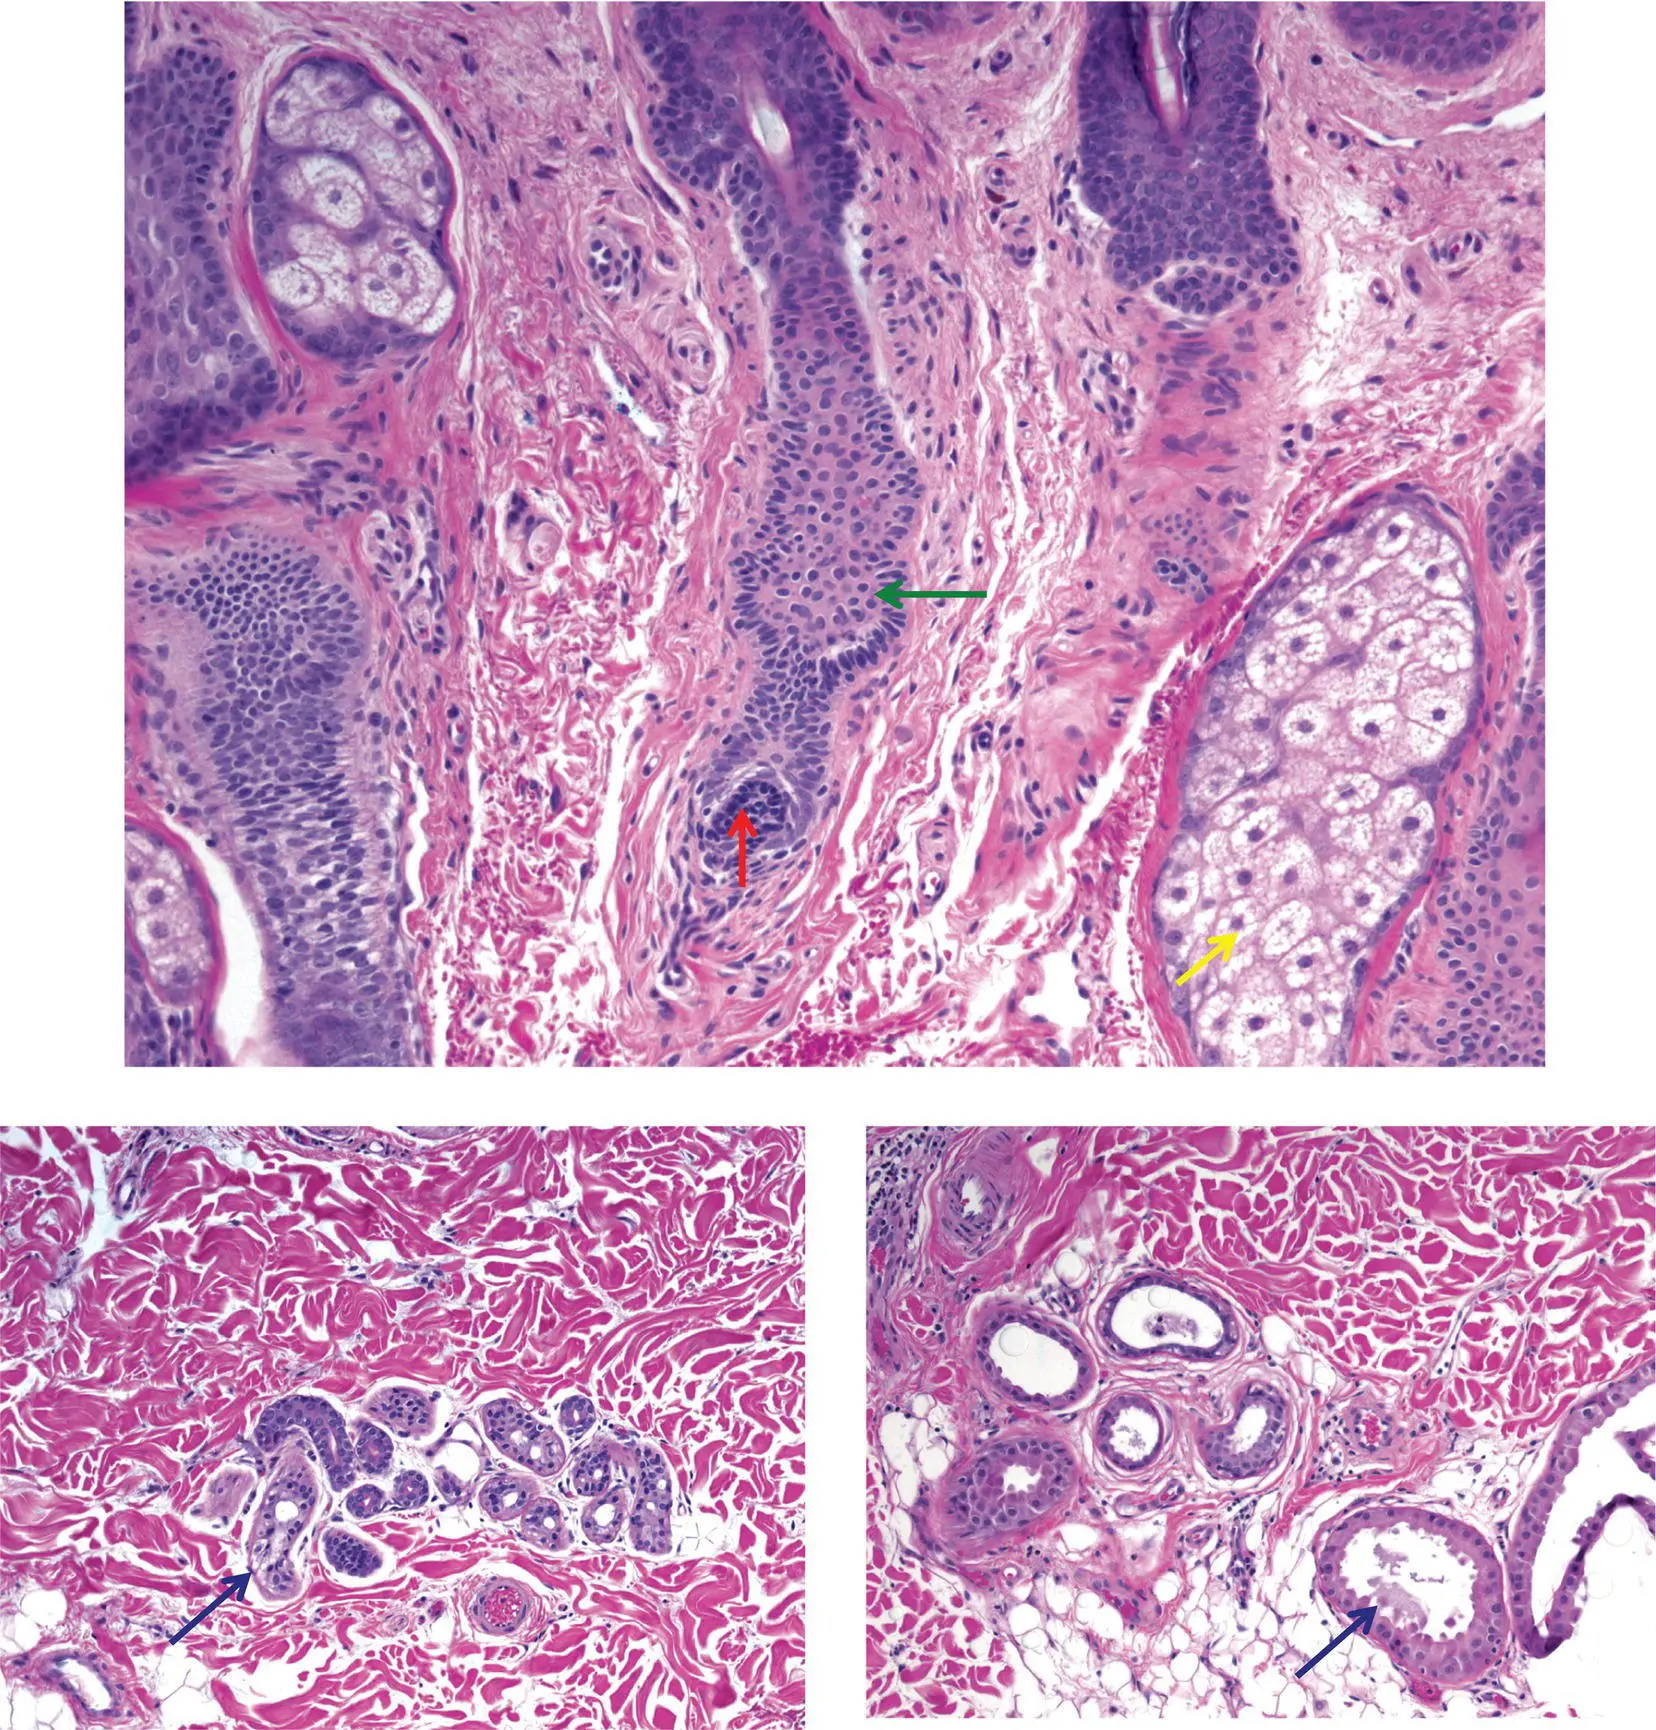

Figure 2(C)Different tumors are predominantly composed of a particular cell type

Hair follicle: matrical cells are round to oval and dark blue (red arrow); outer root sheath cells are pale pink (green arrow)

Sebocytes: bubbly cytoplasm (yellow arrow) and central nucleus that may be star‐shaped (scalloped)

Eccrine gland and duct: the gland has clear cells (blue arrow); the duct has an eosinophilic pink cuticle

Apocrine gland and duct: the gland often shows decapitation secretion (black arrow)